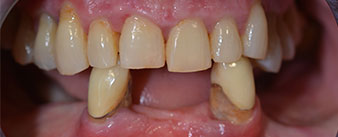

The 64-year-old patient presented with residual dentition of teeth 38, 33 and 43 and a clasp denture in the mandible (Fig. 1 and 2).

The necessary periodontal treatment and extraction in the maxilla was to be performed at a later point in time, as the patient is a teacher and was busy with school leaving exams at the time. She could neither eat nor speak properly, as the temporary prosthesis was very fragile, breaking regularly and under the slightest strain.